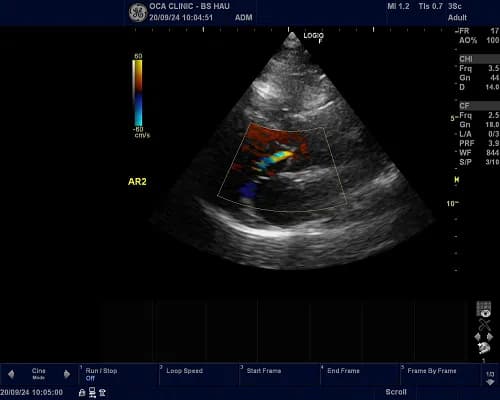

Siêu âm Doppler

Siêu âm Doppler dùng để kiểm tra lưu lượng máu, đo áp lực động mạch phổi . Bác sĩ có thể sử dụng siêu âm doppler màu để lập bản đồ hướng và tốc độ của các dòng máu trong tim.

Thông thường máu chảy về phía đầu dò xuất hiện màu đỏ, máu chảy ra có màu xanh.

Kết quả của siêu âm Doppler có thể kiểm tra, phát hiện một số bệnh tim, mạch máu và đánh giá cung lượng tim.

Hình ảnh sieu âm tim phát hiện bệnh lý hở van 2 lá